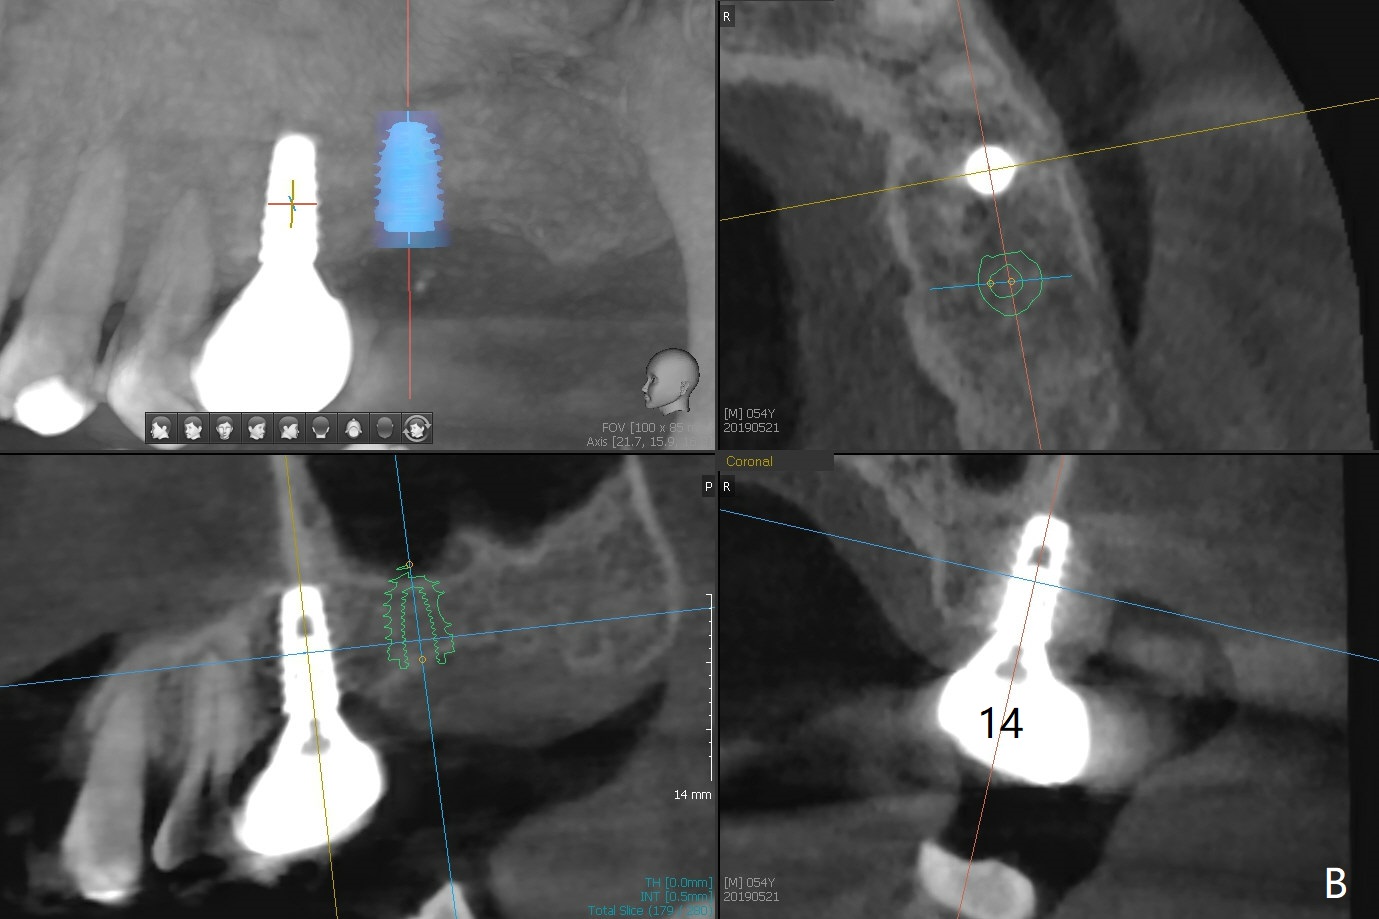

A 54-year-old man remains difficult in mastication in spite of implant placement at #14 and 31 (Fig. A, B, E, including screw loosening (poor trajectory at #14)). In addition to 2 more implants at #15 and 18 with guide, malocclusion seems to be necessary to be addressed (Fig.1-5). It appears that UR, LL4 should be extracted for orthodontic treatment (Fig.6-10). To reduce screw loosening, IS guide will be used to place IBS (5x9mm) and tissue-level (5x11mm) implants at #15 (PRF)and 18, respectively. If the one at #14 or 15 keeps loosening, splint #14 and 15 crowns. In fact the patient agrees with limited ortho (UR7 cross bite).